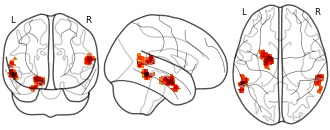

"description": "Multi-modal analysis in BPD. Brain regions exhibiting smaller gray matter and decreased activation during emotion processing in BPD compared to healthy controls. Note: Results were thresholded at p<.0025. Note2: Results were updated (see Erratum for this publication).",